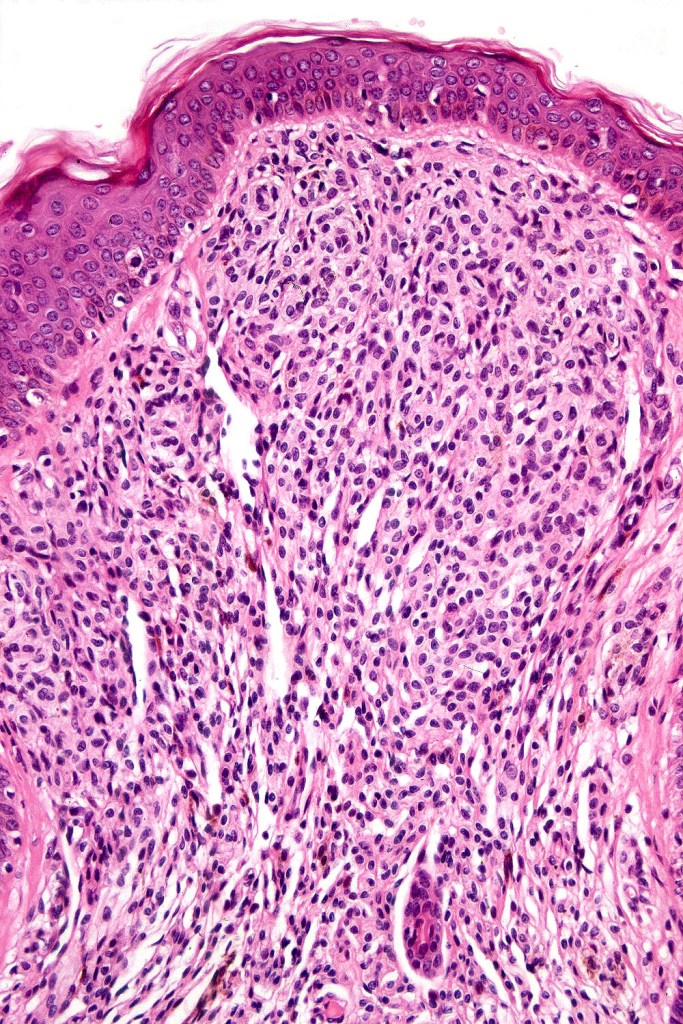

Melanoma arising in a congenital nevus

•Although the vast majority arise in giant forms, they may be encountered in smaller lesions & can be present at birth

•Develop in the dermal component

•Typical melanoma, nevoid melanoma, small cell melanoma, pleomorphic/anaplastic melanoma, melanoma with heterologous differentiation & malignant nerve sheath-like melanoma.

This melanoma arose in a small congenital nevus of the scalp. It metastasized widely. Varying features in different fields.